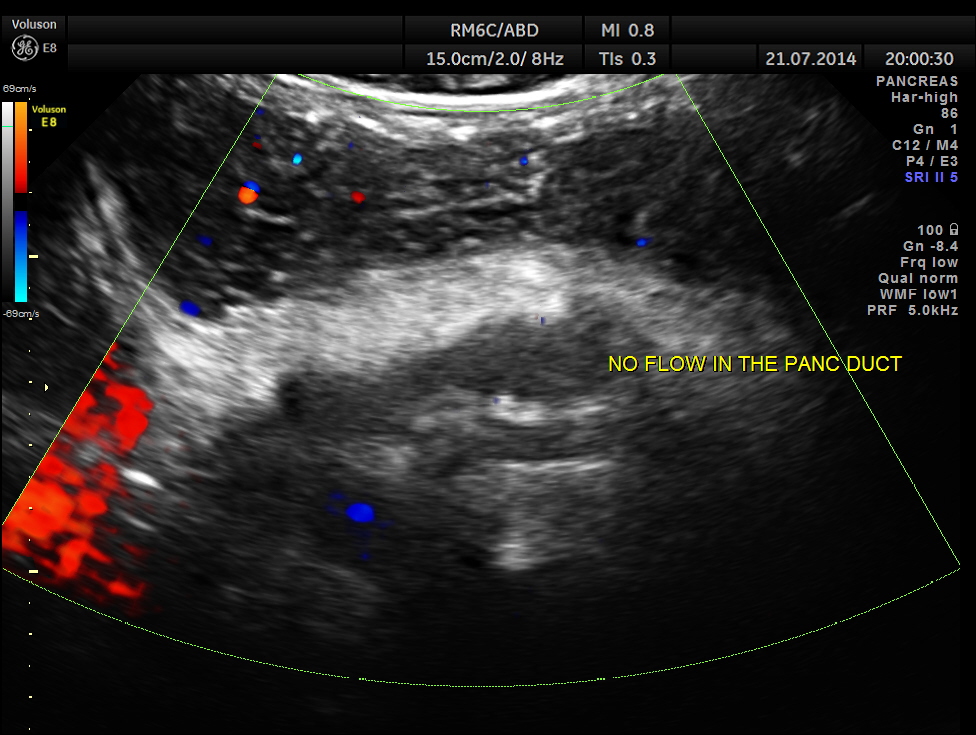

The following pictures show the pancreas.

Pancreatic duct is dilated prominently.

Pancreatic duct dilated.- 12.9 mms.